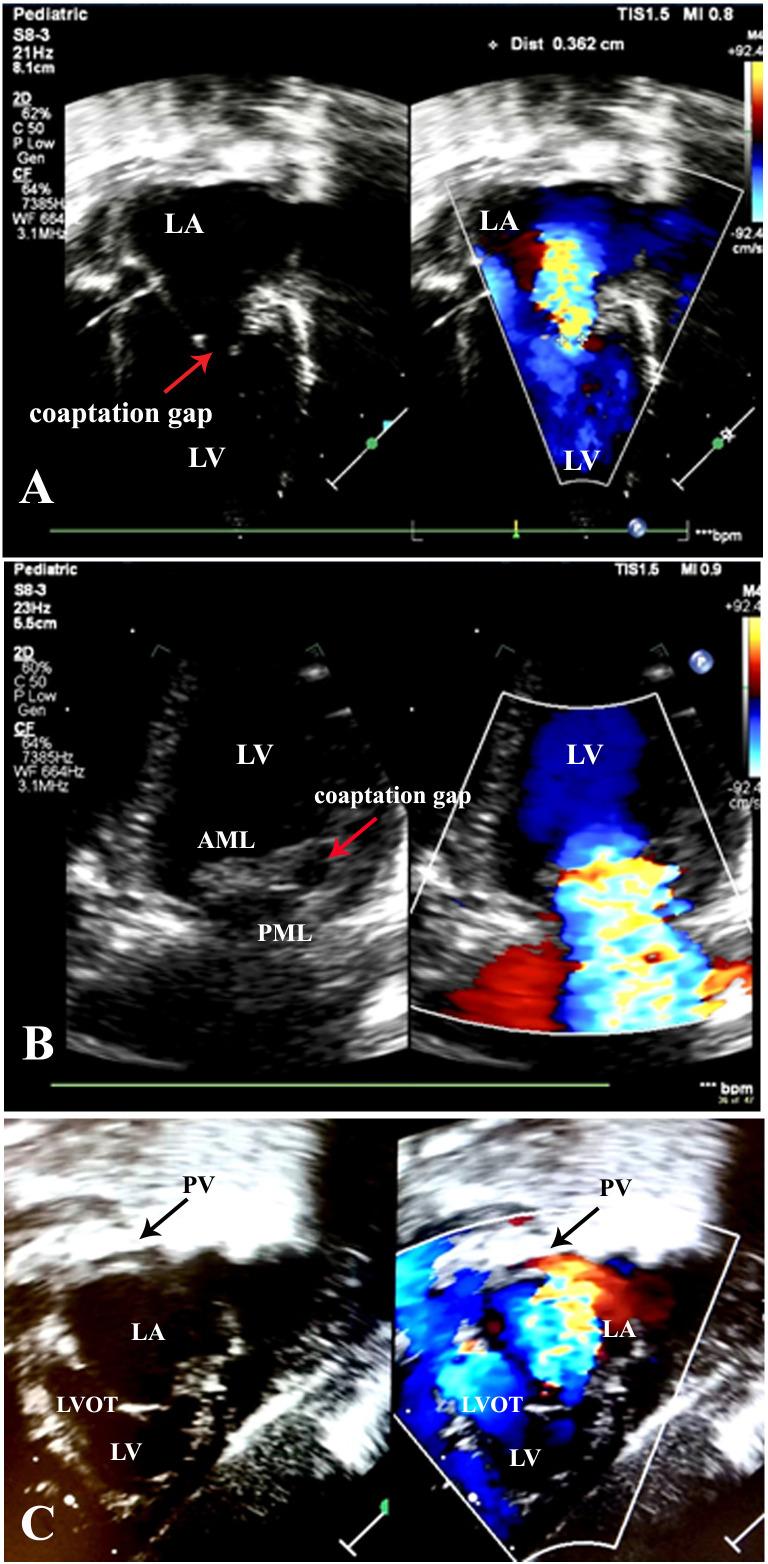

Anomalous mitral arcade (MA) is a rare congenital anomaly. We report a case of MA in a newborn who presented with hydrops fetalis due to severe mitral regurgitation. After birth, he developed severe respiratory failure, congestive heart failure and airway obstruction because an enlarged left atrium from severe mitral regurgitation compressed the distal left main bronchus. There is limited experience in surgical management of this condition in Thailand, and the patient's mitral valve was too small for replacement. Therefore, he was treated with medication to control heart failure and supported with positive pressure ventilation to promote growth. We have followed the patient until the current time of writing this report at the age of 2 years, and his outcome is favourable regarding heart failure symptoms, airway obstruction, growth and development. This case describes a challenging experience in the non-surgical management of MA with severe regurgitation, which presented at birth.

先天性二尖瓣环异常(MA)是一种罕见的先天畸形。我们报告了一例 MA 病例,该病例发生在一名新生儿中,其表现为严重二尖瓣反流导致的胎儿水肿。出生后,他因严重二尖瓣反流导致的左心房增大压迫远端左主支气管而出现严重呼吸衰竭、充血性心力衰竭和气道阻塞。在泰国,这种情况下的手术治疗经验有限,并且患者的二尖瓣太小,无法进行置换。因此,他接受了药物治疗以控制心力衰竭,并使用正压通气来促进生长。我们一直随访该患者,直至撰写本报告时,他已经 2 岁了,其心力衰竭症状、气道阻塞、生长发育情况均良好。本例描述了一种在出生时即出现严重反流的 MA 的非手术治疗具有挑战性的经验。